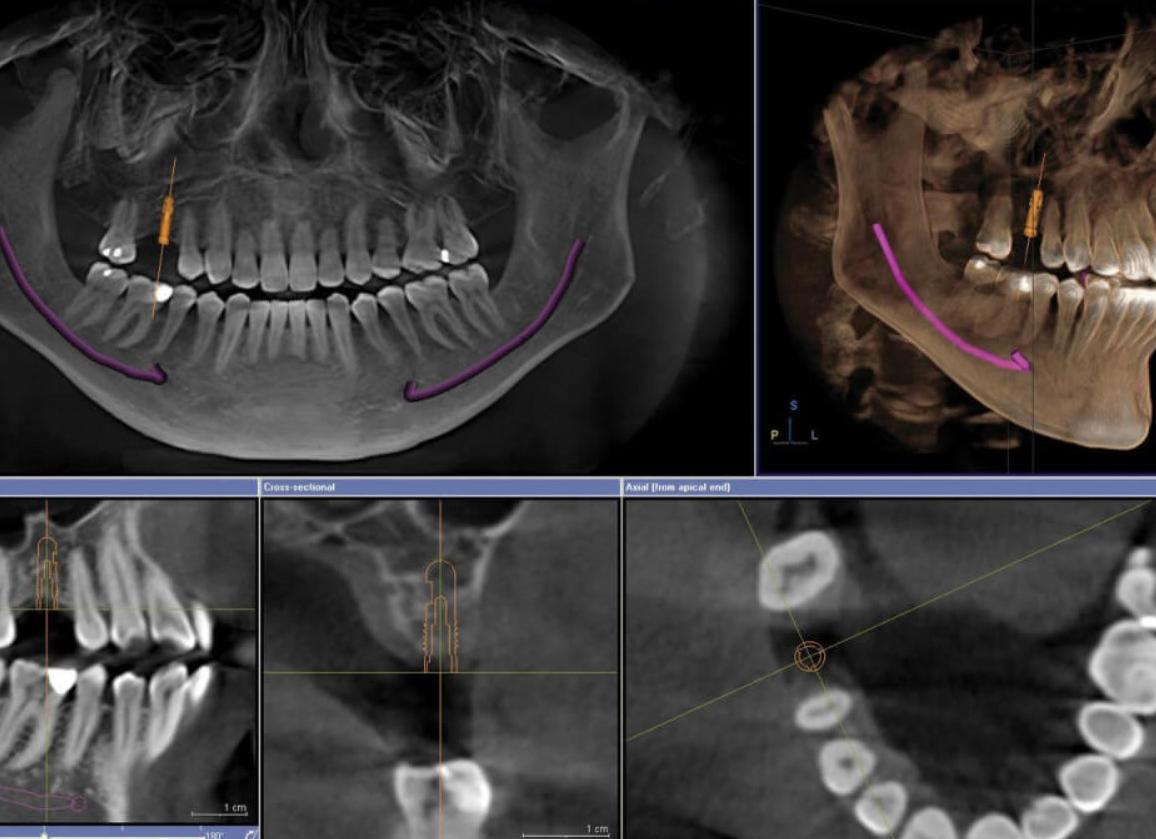

Готовые снимки выдаются пациентам в различных плоскостях, что очень важно для грамотного лечения. Стоит отметить и то, что специальное оборудование помогает реализовать технологию построения трёхмерной модели данной области лица. Компьютерная томография челюстного пространства поможет максимально точно сделать снимок челюсти, причём специалист даже сможет получить данные о высоте и ширине всех элементов. Будет даже возможность нахождения нижнечелюстного канала, а также определения состояния пазухи верхней челюсти. Метод позволит специалисту при помощи одной компьютерной томограммы на ранних этапах выявить опаснейшие заболевания, например, опухоли, а также воспалительные процессы, кисты и патологии. Стоит упомянуть и про возможность контроля имплантации.

КТ челюсти для имплантации зубов определяет:

• Состояние костной ткани челюсти.

• Наличие дистрофии костей челюсти и степень разрушения кости.

• Толщину челюстной кости (если имплантация планируется на нижней челюсти).

• Получить двухмерное изображение челюсти, а при необходимости назначается 3d томография зубов, позволяющая детально рассмотреть проблемный участок со всех сторон.

Что показывает КТ челюсти? Компьютерная томография дает возможность измерить ширину, высоту верхней и нижней челюсти, определить местоположение нижнечелюстного канала, состояние верхнечелюстной пазухи, своевременно выявить кисты, опухоли, воспалительные заболевания, переломы, свищи, патологии височно-нижнечелюстного сустава, осуществить контроль произведенной имплантации.

Компьютерная томография по 3D технологии разрешает получить панорамное сканирование зубочелюстной системы в полном объеме для постановки наиболее точного и верного диагноза, максимально исключив его ошибочность.

3D-изображения дает возможность врачам визуализировать те участки, которые остались «невидимыми» в других исследованиях, позволяет получить данные для имплантации и хирургических операций, определиться  в случаях необходимой пересадки костной ткани в местах имплантации.